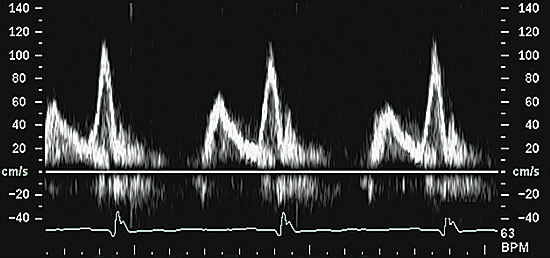

More importantly, Doppler echocardiogra phy is used to evaluate the characteristics of diastolic trans–mitral-valve blood flow. The peak velocities of blood flow during early diastolic filling (E wave) and atrial contraction (A wave) are measured, and the ratio is calculated. Under normal conditions, the early-filling E-wave velocity is greater than the A-wave velocity, and the E-to-A-wave ratio is about 1.5 (Figure 2). In early diastolic dysfunction, this relationship reverses, because the stiffer heart relaxes more slowly, and the E-to-A-wave ratio drops below 1.0 (Figure 3). As diastolic function worsens and left ventricular diastolic pressure rises, left ventricular diastolic filling occurs primarily during early diastole, because the left ventricular pressure at end-diastole is so high that atrial contraction contributes less to left ventricular filling than normal. At this point, the E-to-A-wave ratio rises, often to greater than 2.0 (Figure 4). This so-called “restrictive pattern” confers a poor prognosis.21 Recent studies also have shown that Doppler evaluation of myocardial velocities during ventricular relaxation predict elevated filling pressure.

FIGURE 4.

Trans–mitral-valve Doppler flow pattern in a patient with severe (restrictive) diastolic dysfunction. The E-to-A-wave ratio is abnormally high, and the A-wave velocity is extremely low.